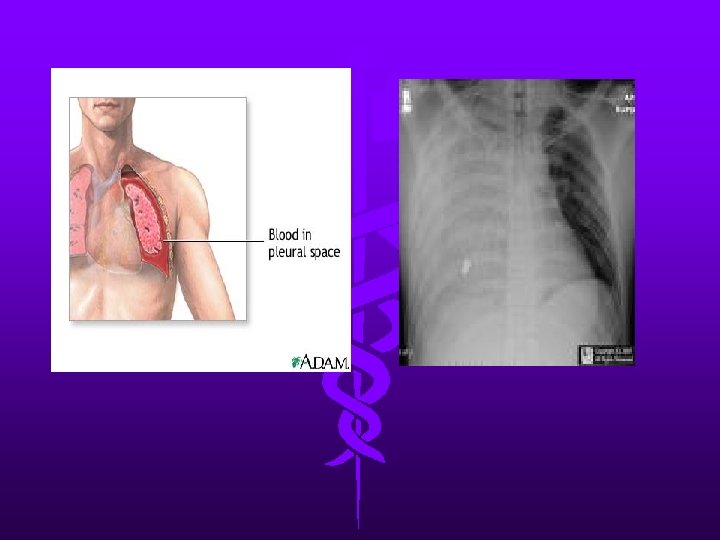

Hemothorax • Can be caused from bleeding of intercostal vessels, pulmonary arteries or veins, avulsion of mediastinal vessels or penetrating cardiac injury. • Differentiated from pneumothorax by dullness to percussion with absent breath sounds

Hemothorax • The choice and dose of anaesthetic induction agent is determined by the severity of the shock and any preexisting medical co-morbidity • Fluid load before chest tube placement • Thoracotomy may be needed if drainage is more than 250 mls per hour, or the patient’s physiological status continues to deteriorate despite fluid replacement.